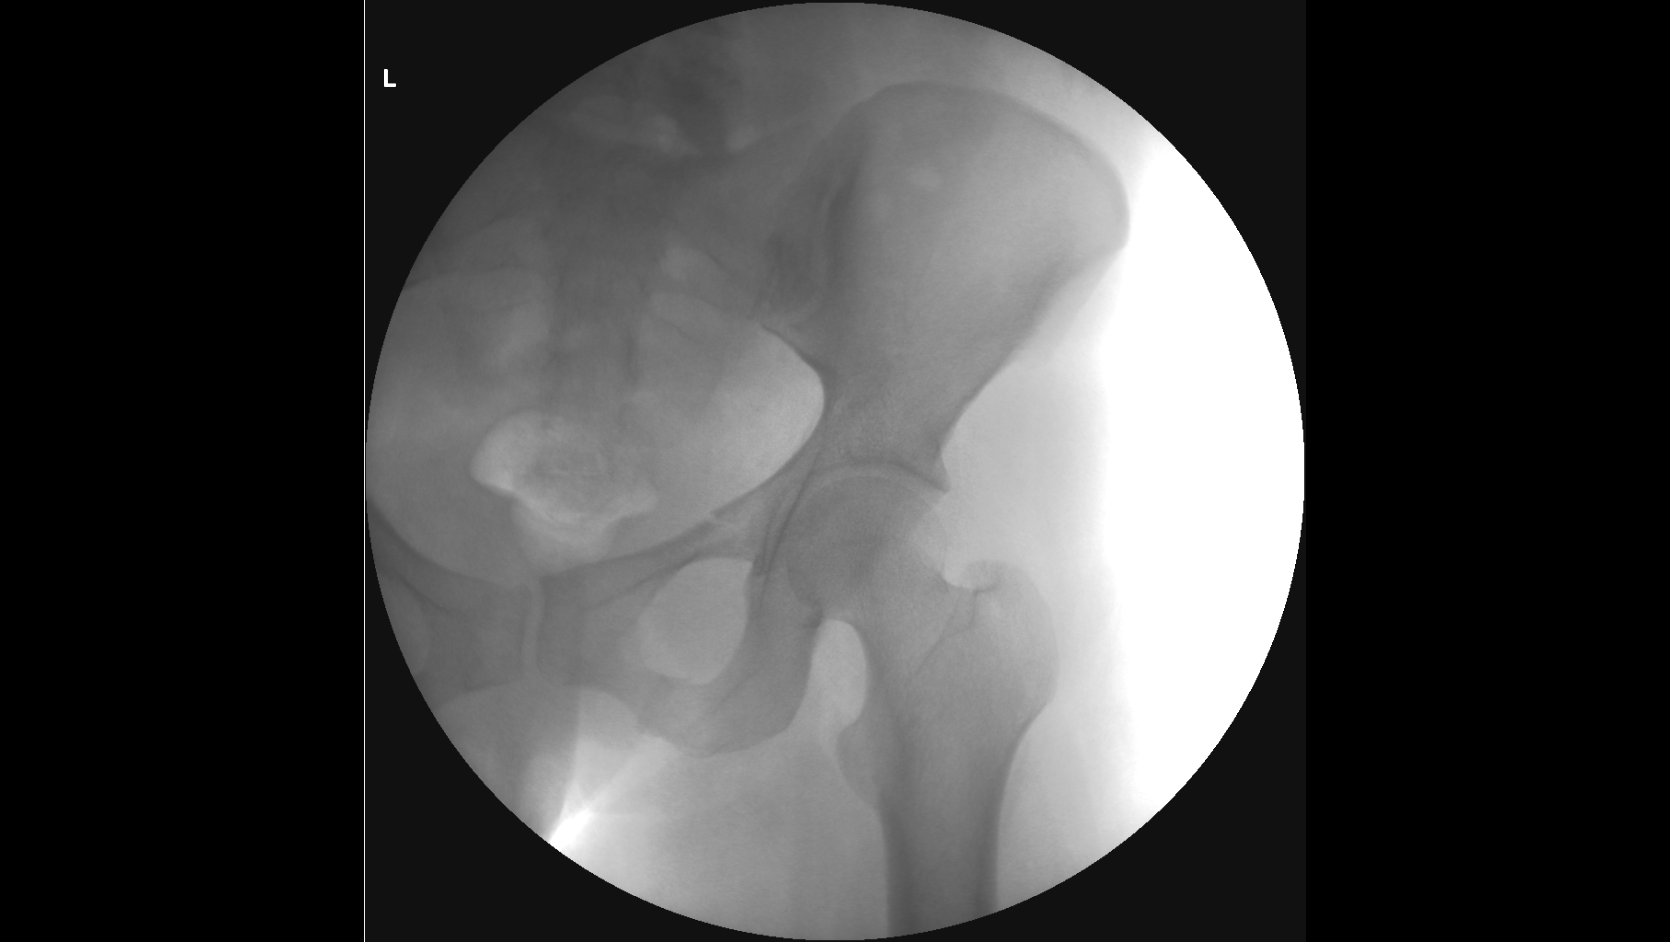

По вашей рекомендации я написал ходатайство о проведении повторной комиссионной экспертизы и сам в ней участвовал, так как разобрался с вашей помощью во всех деталях, практический, все включая следователя были уверены, что вред квалифицируют, как средней тяжести, но по результатам повторной экспертизы, каким то странным образом эксперты нашли еще один третий перелом правой лобковой кости, в результате чего вред здоровью стал действительно Тяжким.

Посмотрите, пожалуйста, третье заключение экспертизы, а то закрадывается сомнения о том, что смотрели три рентгенолага и установили три разных диагноза, и правильно ли они определили третий перелом.

Отправляю заключение комиссионной экспертизы и рентгенные снимки сразу после происшествия и по истечению двух месяце.

снимки сразу после аварии, через 2 месяца и через 3 месяца

На рентгенограммах хорошо видны переломы: правой лонной и правой седалищной костей, левой лонной кости. Перелома левой седалищной кости нет. "Условная граница" левой лонной и левой седалищной костей, на самом деле, находится на некотором расстоянии от места перелома левой лонной кости. Т.е. ссылка экспертов на прохождение линии перелома по этой условной границе представляется изрядно притянутой и, в любом случае, это непосредственно не свидетельствует о наличии перелома левой седалищной кости. Для оценки этой травмы как тяжкий вред нужен перелом типа "бабочки" всех четырех костей: правой лонной (он есть), правой седалищной (есть), левой лонной (есть), левой седалищной (нет!).

Убежден, что за такой перелом тяжкий вред давать неправильно. Это - вред здоровью средней тяжести (по п.7.1 вышеуказанного документа).

Путаница в сторонах переломов: на одном снимке противоположная сторона переломов верхней ветви лонной и ветви седалищной кости обозначена R, на остальных - L. Это может быть принципиальным. В остальном согласен: 6.1.23. отсутствует.